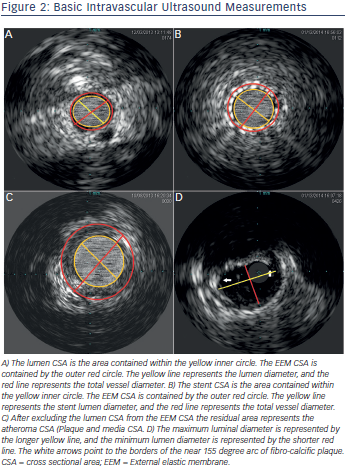

Various studies have demonstrated advantages of IVUS guided interventions when compared to angiography.1–12 An analysis Image titleof the Strategy and intracoronary ultrasound-guided PTCA and stenting (SIPS) trial4 noted a 60.9 % probability that IVUS was less expensive and more effective when compared to angiographic guided interventions. Similarly, Gaster et al. demonstrated decreased cost with an IVUS guided intervention strategy.5 Intravascular ultrasound confers improved accuracy for lesion quantification (e.g. lumen, vessel wall and plaque diameter, area, length, shape and volume), and morphology assessment (e.g. aneurysms, bifurcations, ostial lesions, fibrosis and calcification patterns, filling defects, thrombus, intimal disruption, dissection and ulceration). Additionally IVUS shows the calcium distribution pattern within the vessel wall.13 IVUS is also more accurate than angiography for assessment of eccentric lesions.14 IVUS can aid in the identification of the culprit lesion in unclear cases and clarify the mechanism of Stent thrombosis (ST) or in-stent restenosis (ISR).15,16 Distal embolisation or peri-procedural myocardial infarction (MI) during interventions may be predicted with the IVUS presence of ruptured plaque and large plaque burden in acute coronary syndrome (ACS) and non-ACS patients.17 Greater attenuation angle (>180 degrees), and attenuation length >5 mm seem to be independent predictors for microvascular obstruction in ST segment elevation myocardial infarction (STEMI) patients undergoing primary PCI.18 Pre-emptive use of filter wires in these patient subgroups may prove beneficial. Table 2 and Figure 2 show common IVUS measurements and morphologic findings.